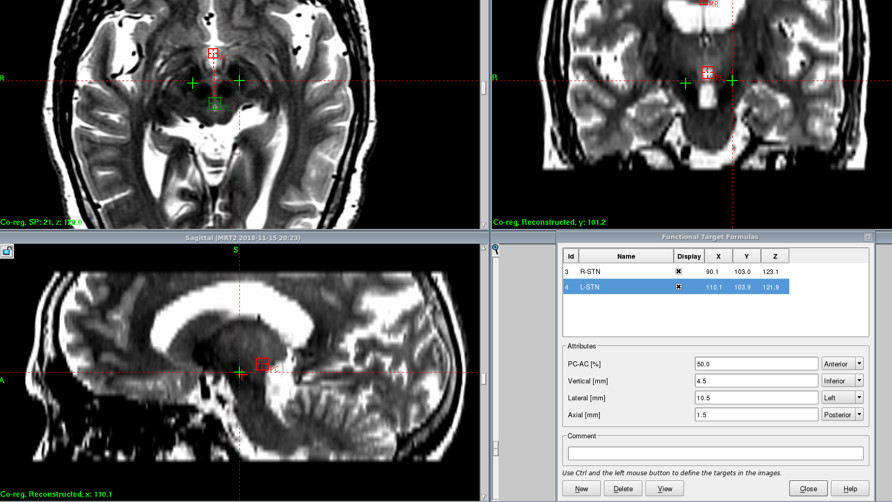

增强3D-T1 bravo。

显示静脉血管。

与定位序列融合。

设计电极穿刺路径,确定头皮切口及颅骨钻孔位置。

从脑回穿刺。

避开大脑皮层回流静脉。

避开基底节区穿支血管。

减少出血风险,确保手术安全!